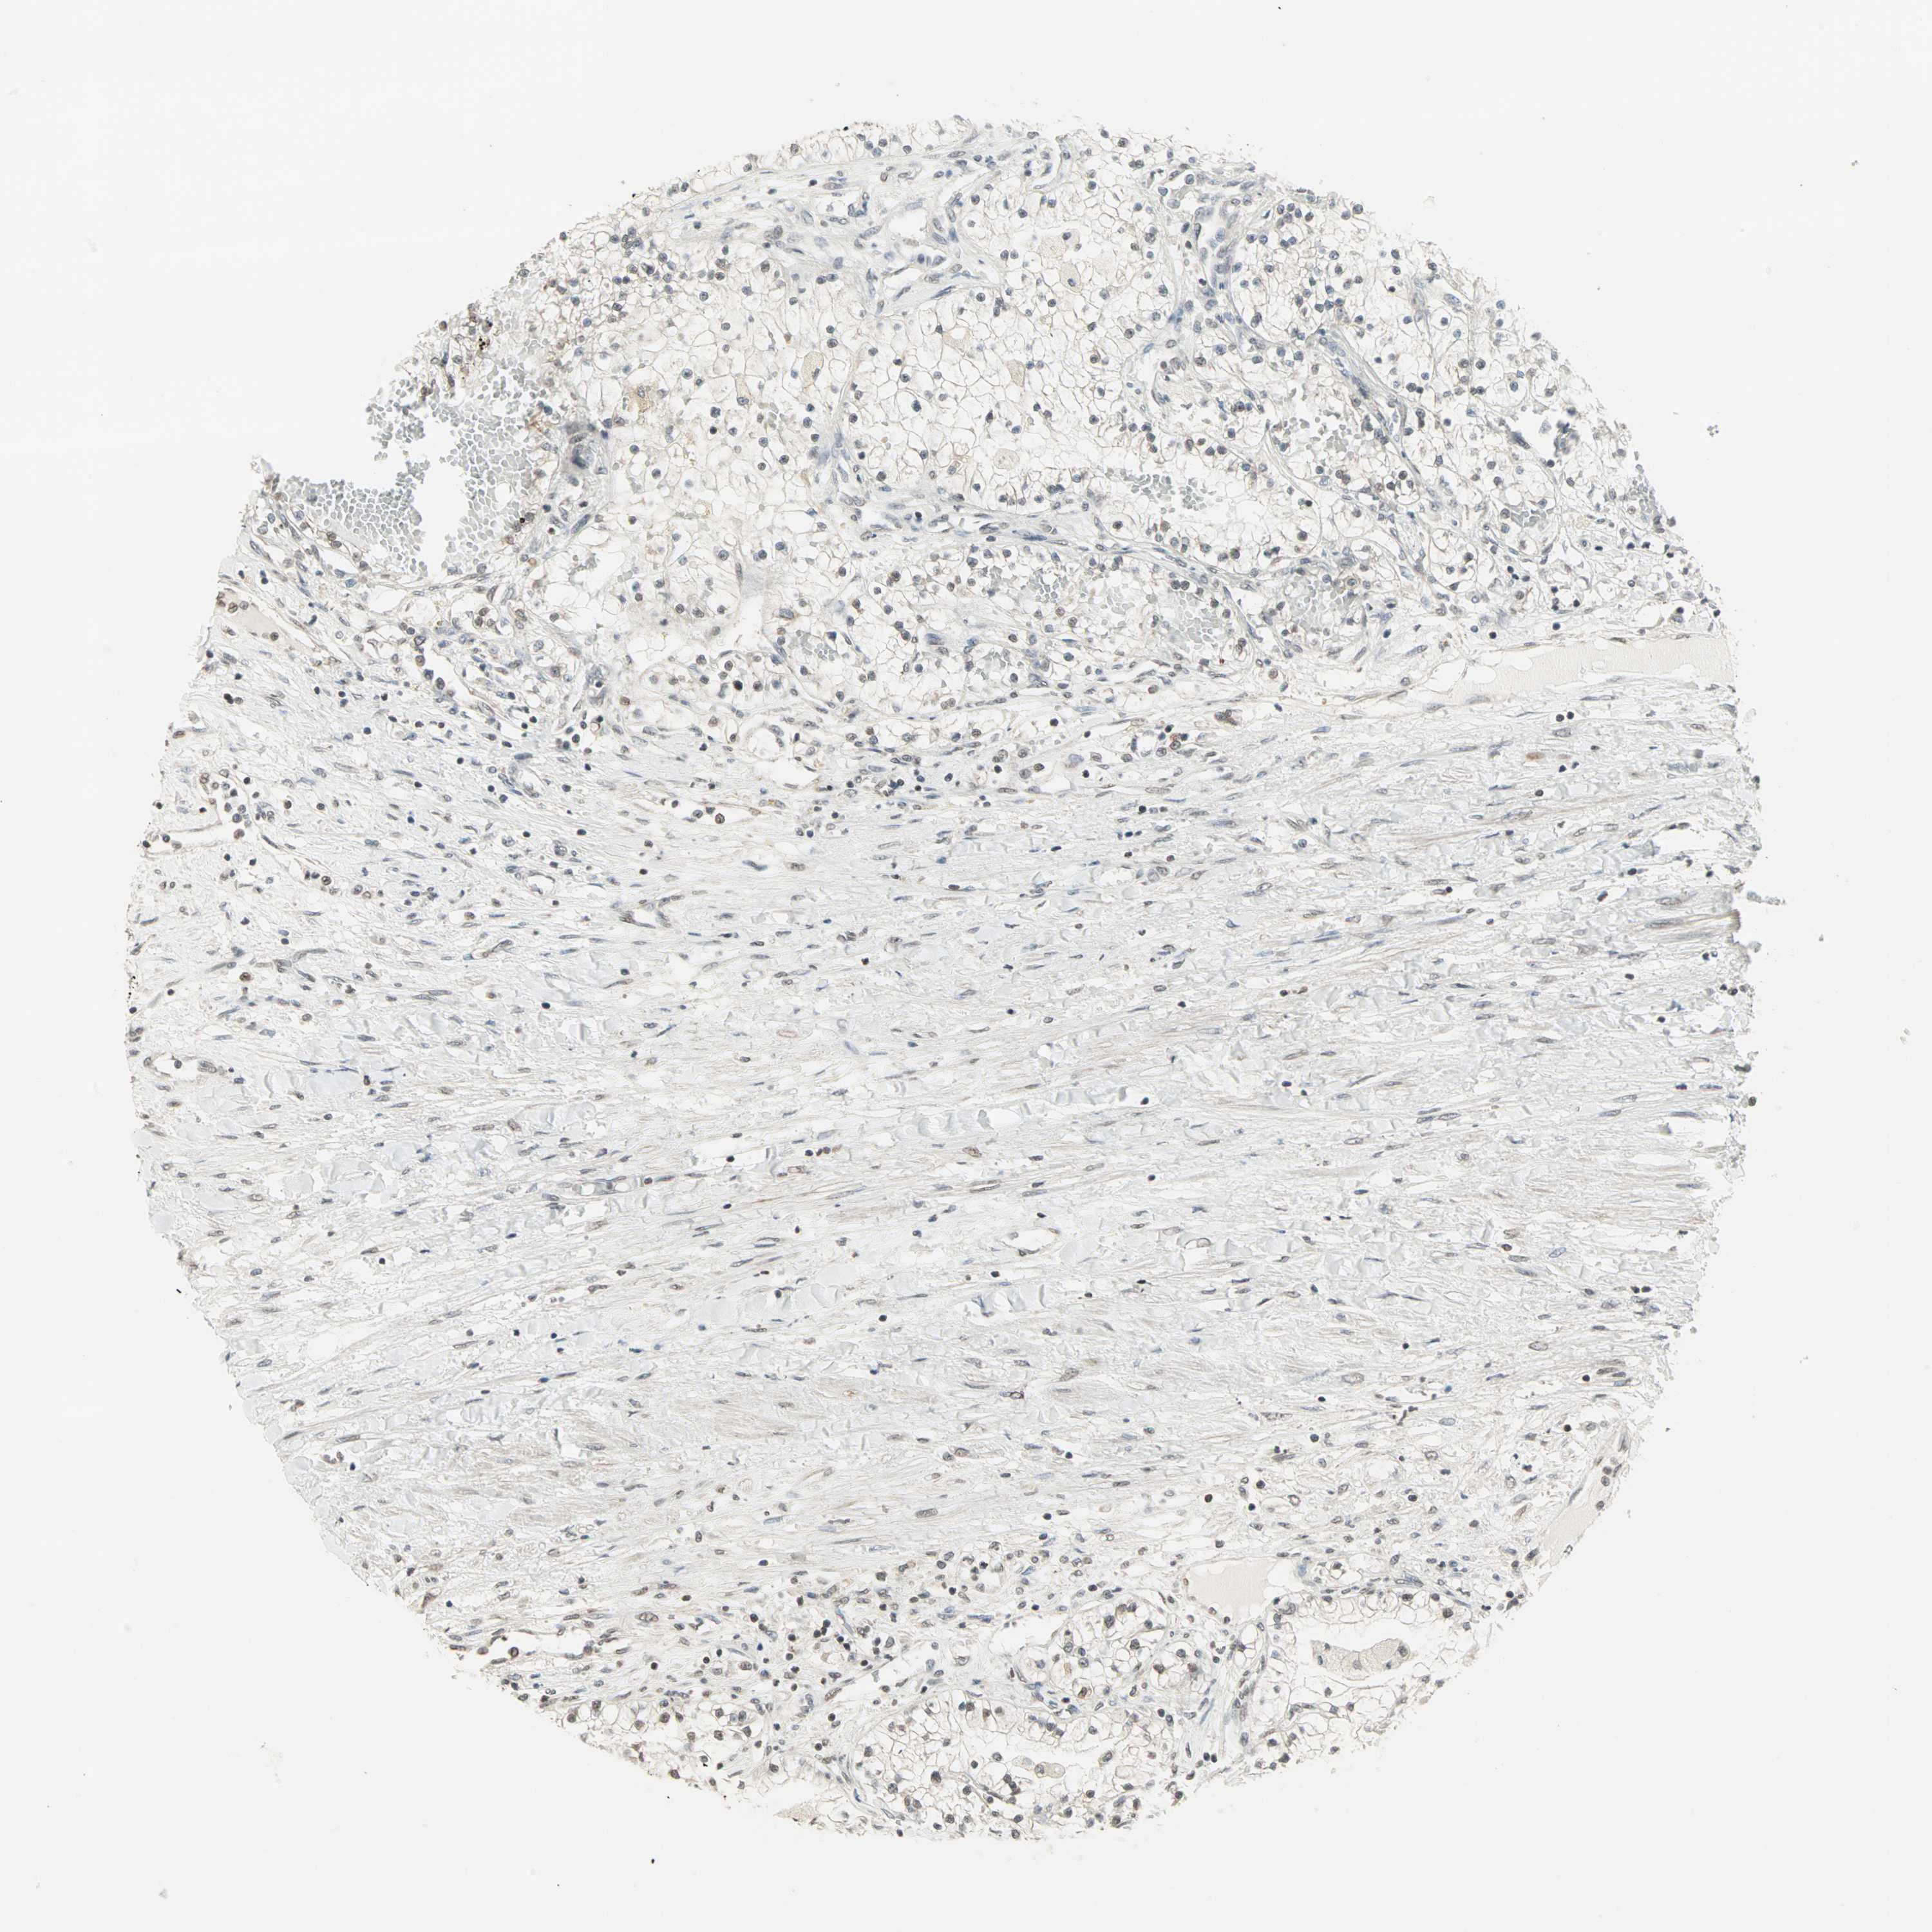

CANCER RENAL CANCER Show tissue menu

KICH TCGA KIRC TCGA KIRC VALIDATION KIRP TCGA PROTEIN RCC CPTAC PROTEIN EXPRESSION